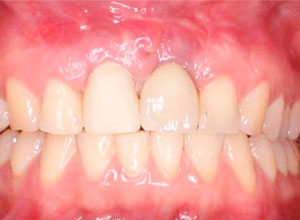

Dejamos que el implante se oseointegre para terminar con la rehabilitación protésica.

Nótese la colocación de los postes y el respeto a la forma de los tejidos gingivales y las papilas, muy importante para obtener el resultado estético final.

Provisionalización para el manejo de tejidos blandos

Colocación de prótesis de zirconia y cerámica